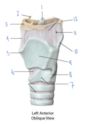

Which structure is labeled by #7?

Cricothyroid ligament

Which structure is labeled by #7?

Cricoid cartilage

(Also #9)

Which structure is labeled by #9?

Cricoid cartilage

(Also #7)